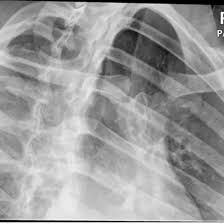

X-Ray Left Sterno Clavicular Joint PA Oblique

An X-ray Left Sterno-Clavicular Joint PA Oblique Scan is an imaging test that shows the left sternoclavicular (SC) joint—where the collarbone meets the sternum—at an angled view. It helps visualize the joint clearly by reducing overlap from other chest structures.

An X-ray Left Sterno-Clavicular Joint PA Oblique can detect joint dislocation, fractures, arthritis, inflammation, or abnormalities from trauma or degenerative conditions.